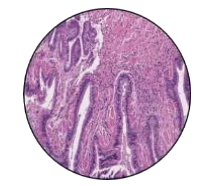

53-year-old male presented to a tertiary care centre elsewhere with complaints of high-grade fever not associated to chills/rigor, productive cough with copious amount of white coloured sputum, breathing difficulty on exertion MMRC Grade III, noisy breathing, chest pain and multiple episodes of haemoptysis. Patient had no other co-morbidities/symptoms of any chronic illness or any other contributary past history. After getting admitted and primary investigations, he was treated with IV antibiotics suspecting pneumonia. After 7 days of treatment patient was referred to our centre as there was no resolution. On clinical examination, patient had shift of trachea to the right side, dullness on percussion, bronchial breath sound and crepitations in the right infraclavicular area. Blood investigations showed leucocytosis (14,000/mm3), elevated levels of ESR (85mm/hr) and CRP (102mg/dl) with no other significant biochemical changes. Chest X-ray taken showed a collapse of the right upper lobe, with the classical ‘Golden S’ sign (figure 1) which raised a suspicion of right upper lobe mass. Further HRCT thorax was taken which showed a ‘bronchial cut off’ sign (figure 2) and an enhancing soft tissue lesion in the right upper lobe with encasement right pulmonary artery and bronchus (figure 3). Patient was taken up for bronchoscopy which showed a right upper lobe mass (figure 4). Bronchial brushings and biopsy (figure 5) were taken and samples were sent for Histopathological study which confirmed Non-Small Cell Carcinoma- Adenocarcinomatous type (figure 6).

Figure 1: Chest-Xray

Figure 1